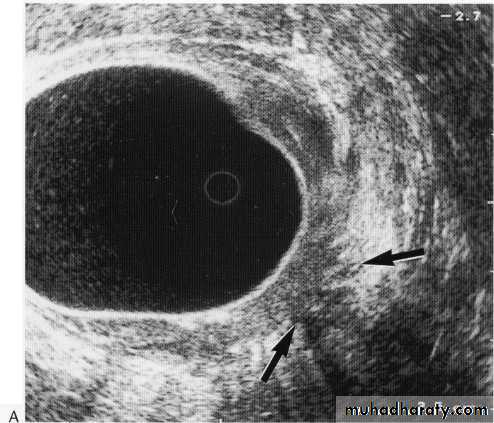

Leiomyoma EUS